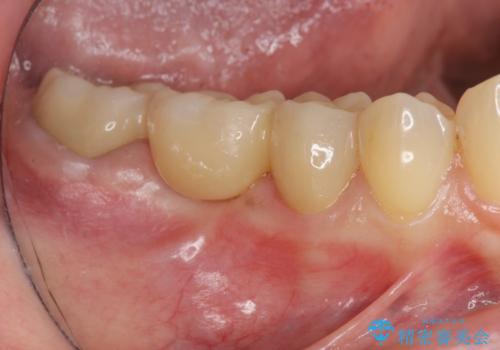

銀歯の下に大きな虫歯の再発

「 セラミック治療 」奥歯を白くしたい